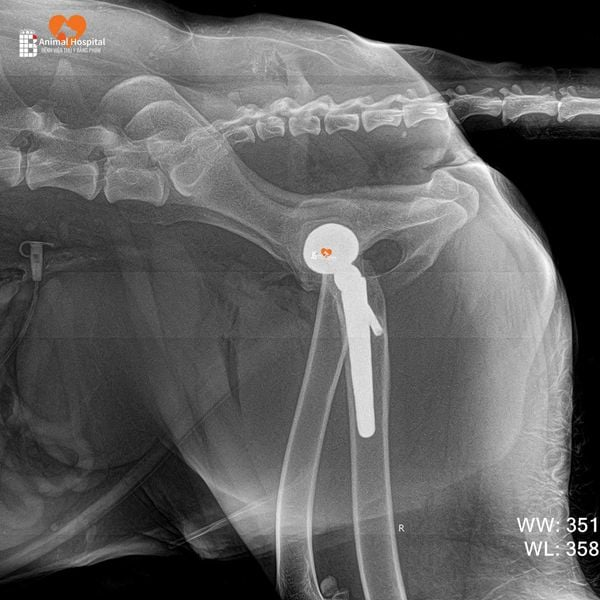

Dịch Vụ Thay Khớp Háng Nhân Tạo (Total Hip Replacement – THR)

Dưới sự phụ trách chuyên môn của Giám đốc Phạm Bằng – được chứng nhận chính thức trong phẫu thuật Thay Khớp Háng Toàn Phần của BlueSAO cho chó và mèo (Total Hip Replacement – THR), bệnh viện áp dụng kỹ thuật chỉnh hình tiên tiến hàng đầu thế giới nhằm điều trị hiệu quả các bệnh lý nặng ở khớp háng như thoái hóa, trật khớp bẩm sinh hoặc gãy cổ xương đùi.

Phẫu thuật THR cho thú cưng là kỹ thuật đòi hỏi trình độ cao, hệ thống thiết bị hiện đại và đào tạo bài bản theo chuẩn quốc tế. Với nền tảng vững chắc trong ngoại chấn thương chỉnh hình thú y và chứng chỉ quốc tế sau khóa đào tạo THR, anh Bằng đã thực hiện thành công nhiều ca thay khớp háng toàn phần, giúp các bé thú cưng giảm đau, phục hồi vận động và nâng cao chất lượng sống.